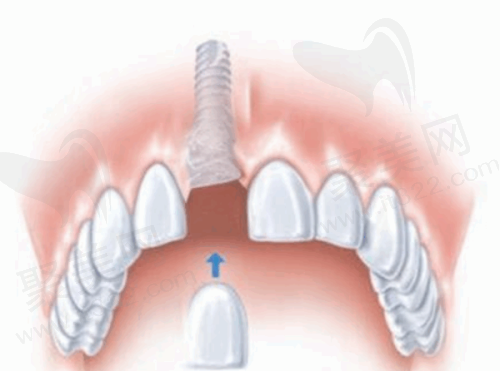

这可是侯家塘店的一大亮点。韩国植牙首颗只需298元(卫健委可查PDY006868号),这个价格非常实惠。不过,它是有一定限制条件的。首先,这是首颗韩系植体的价格,并且要求患者的骨量达标,比如牙槽骨高度要大于8mm,没有牙周病,而且更好是非前牙美学区,后牙咀嚼功能区做这个活动更划算。

这个低价源于两大支持,一方面是湖南种植牙集采落地后,韩国奥齿泰植体采购价降至900元/颗,降幅达到了70%;另一方面叠加了“口福行动”公益,所以首颗能探底到298元,不过每个月限量50颗。这个活动包含韩国植体、手术费、基台和国产冠,但不包含骨粉、上颌窦提升等复杂附加项目。就像长沙的张阿姨,因为骨量不足,被迫加做植骨,多花了3000元,所以大家务必先拍CT评估自己的情况。

在种植技术方面,医院采用了CAD导航微创种牙技术。这种技术就像是给医生装了一个“导航系统”,能让医生更精细地植入种植体,减少手术创伤,缩短手术时间,患者术后修复也更快。而且,医院的穿颧种植技术可以解决无骨难题,让那些原本因为牙槽骨条件不好而无法种牙的患者也能拥有健康的牙齿。